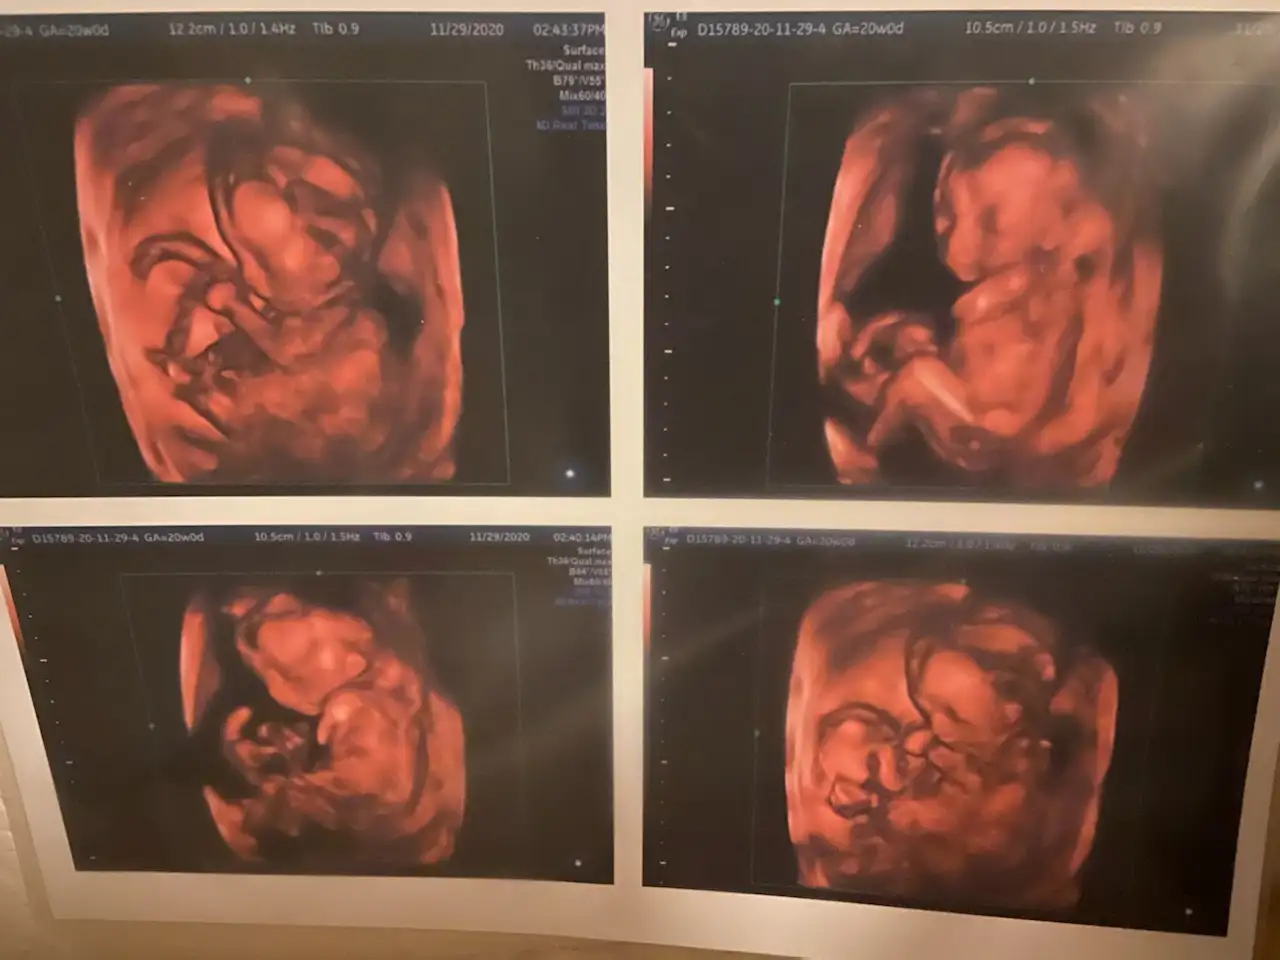

So, when Tinamarie Costales and John Flores found out about six months into the pregnancy that Thessa had trisomy 18, they faced the first of several difficult decisions.